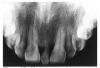

Dentin caries extends into the tooth dentin and can be recognized by noting the focal loss of dentinal radiopacity. Most commonly, this darkened dentin is located beneath carious enamel and, typically, the lateral dimension of the dentinal involvement exceeds that of the associated enamel caries (Figure 3). Dentin caries may be discerned interproximally, on the occlusal surface, buccally/lingually, or on root surfaces.

Figure 3 - Dentin Caries

Figure 3